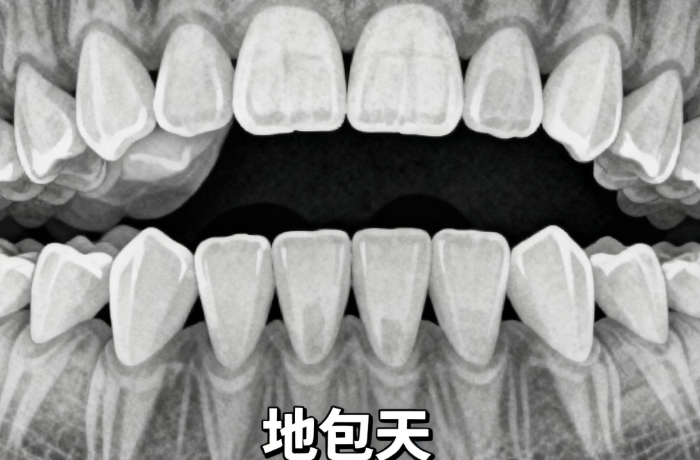

有沒有骨性牙凸、地包天的姐妹?舉個手讓我看看!是不是跟我以前一樣,跑了好幾家醫(yī)院,醫(yī)生都說“骨性矯正難度大,可能要手術(shù)”“矯正效果有限,做好心理準備”?作為過來人太懂這種心情了:既怕手術(shù)遭罪,又不甘心帶著凸嘴過一輩子。直到我刷到許天民教授的患者案例,才發(fā)現(xiàn)原來骨性矯正也能不用遭大罪、效果還超驚艷!今天就把我整理的許天民教授真實患者評價和核心優(yōu)勢分享給大家,骨性整牙黨直接抄作業(yè)!

簡單說,傳統(tǒng)骨性矯正要么靠打骨釘(侵入性,有風(fēng)險還疼),要么療效差。但許醫(yī)生的技術(shù)能利用我們自己口腔的生理力量來矯正,減少骨釘使用,甚至很多實例不用打骨釘就能實現(xiàn)牙齒內(nèi)收,既可靠又舒服,療程還能縮短。這也是為啥他的患者里,很多都是被其他醫(yī)生判“高難度”的骨性實例。